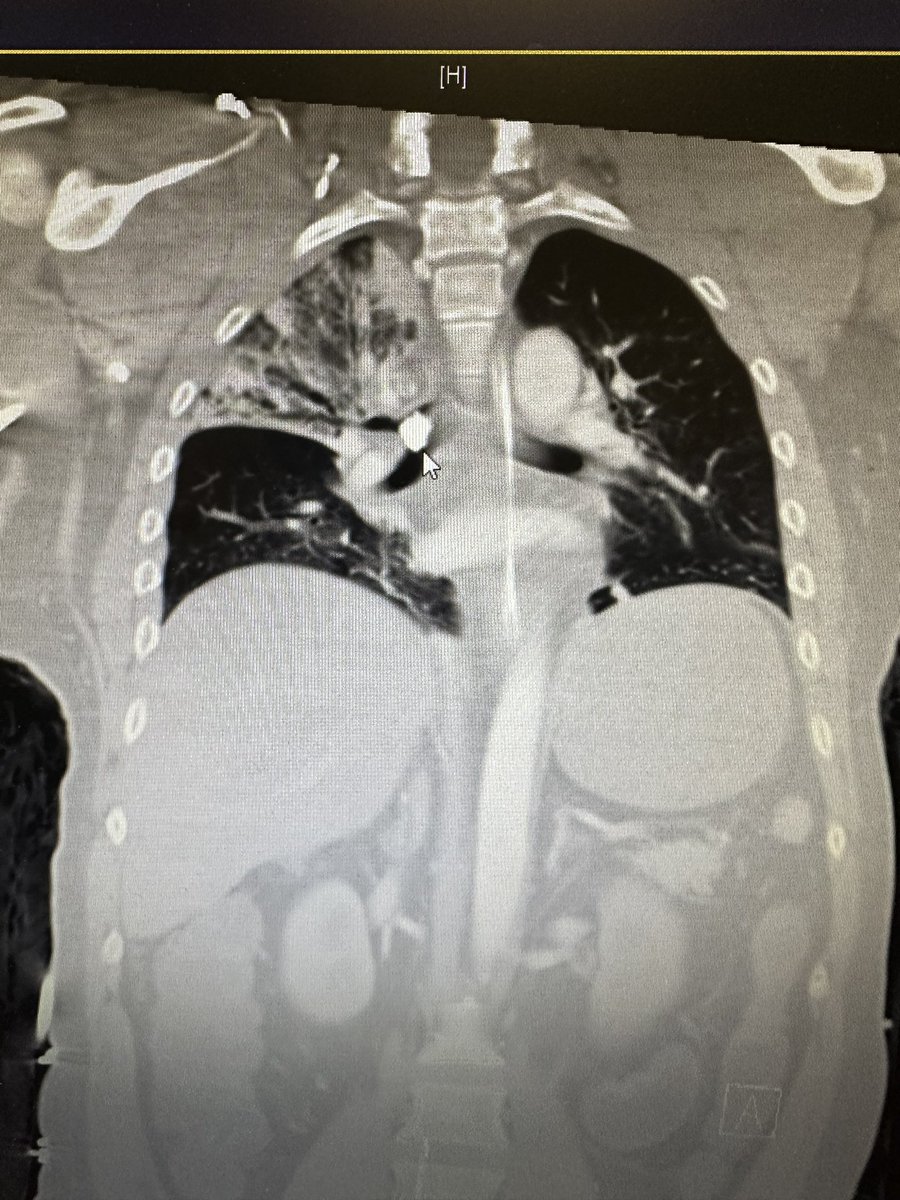

Just another day in the neuro icu! 🎣 Foreign body removal ( rock) with a flexible bronch! Extracted with a retrieval basket + tube exchange given its large diameter. #neurotrauma @HuimahnChoi @UTH_Neurocrit